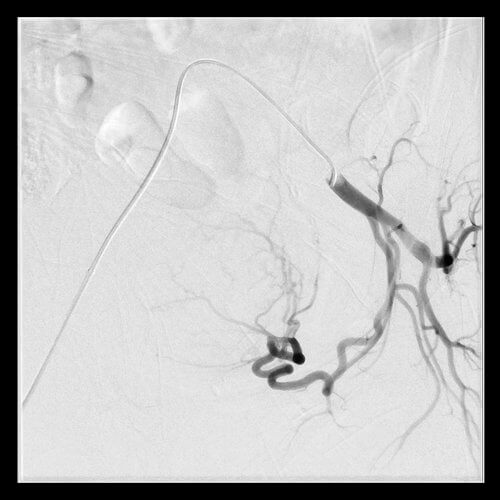

42 year old female who presents with abnormal bleeding, menstrual cramping, and frequent urination and subsequently undergoes UFE.

42 year old female who presents with abnormal bleeding, menstrual cramping, and frequent urination and subsequently undergoes UFE.